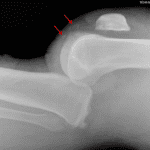

- Posterior knee dislocation

- Several tiny ossific fragments project anterior to the femoral condyles

- Irregularity of the articular surface of the inferior pole of the patella

- High position of the patella

- Large joint effusion

- Soft tissue swelling about the knee

- Posterior knee dislocation

Posterior knee dislocation. Consider CTA if there is concern for associated vascular injury.

Several tiny ossific fragments project anterior to the femoral condyles, which may represent acute chip/avulsion fractures. These could also be further assessed with CT.

Irregularity of the articular surface of the inferior pole of the patella concerning for nondisplaced fracture.

High position of the patella raises concern for patellar tendon rupture.

Large joint effusion.

Soft tissue swelling about the knee without radiopaque foreign body.